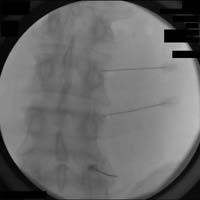

Anterior-posterior fluoroscopic view of a RF neurotomy procedure